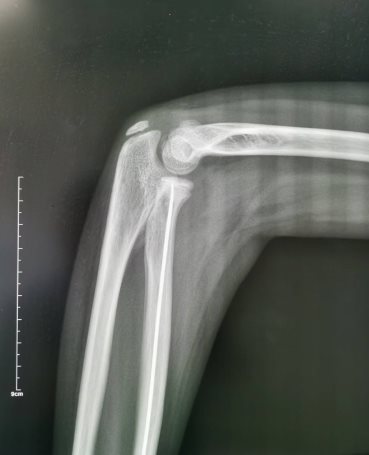

患儿,女,11岁,5月14日因“外伤后右肘肿痛1小时余”入院,术前X线提示右侧桡骨颈骨折,O’Brien分型Ⅱ型,入院后我科陈义权主任立即和张浩医生采用中医特色骨折夹板固定骨折处,于5月17日予右桡骨颈骨折闭合复位弹性髓内钉内固定术,术中我科陈义权主任采用Metaizeau技术,在腕部做一长约1cm切口,利用弹性髓内钉闭合复位骨折端。术后3月复查,骨折端基本愈合。我科成功将中医特色治疗与小儿骨折微创治疗技术完美结合。

图1:术前夹板固定后的X线片